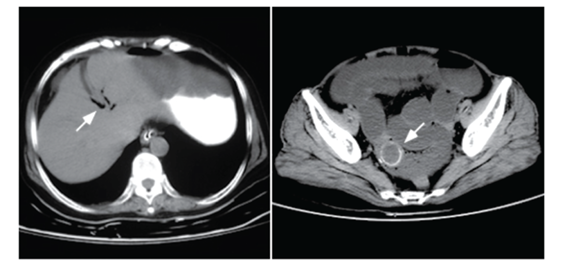

Paciente de 72 anos vem ao PS com distensão abdominal, com parada de eliminação de gases e fezes e com vômitos há 3 dias. Antecedentes pessoais de hipertensão e diabetes. Refere na história crises prévias de dor epigástrica em cólica e febre. Ao exame físico geral, apresentava-se desidratado +/4+, com sinais vitais normais e anictérico. Abdome com leve distensão e dor difusa a palpação profunda, com RHA pouco aumentados. Toque retal sem fezes na ampola retal. Solicitado uma TC de abdome.

Imagens do caso: Radiopaedia.